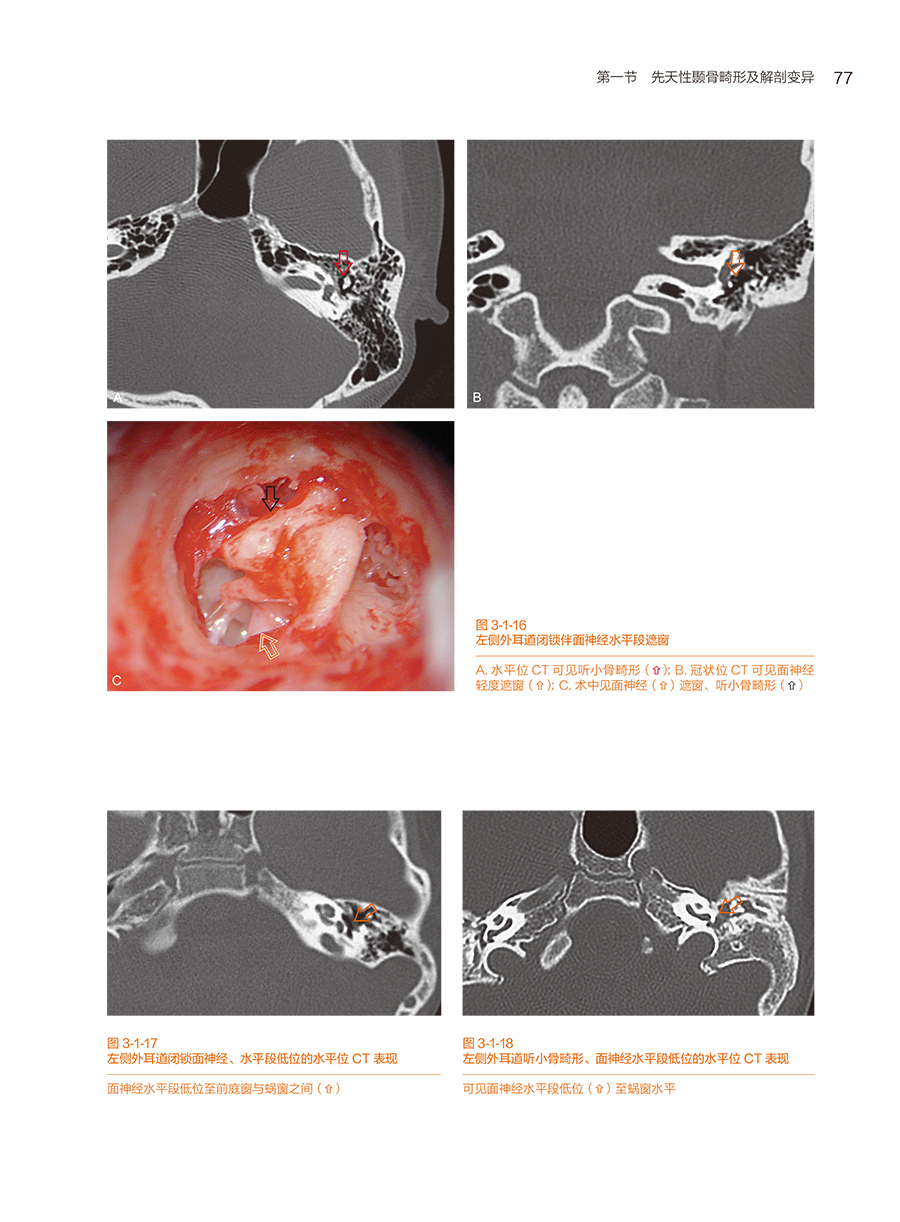

第一节 先天性颞骨畸形及解剖变异

一、先天性外耳道闭锁(或狭窄)伴中耳畸形及术后并发症